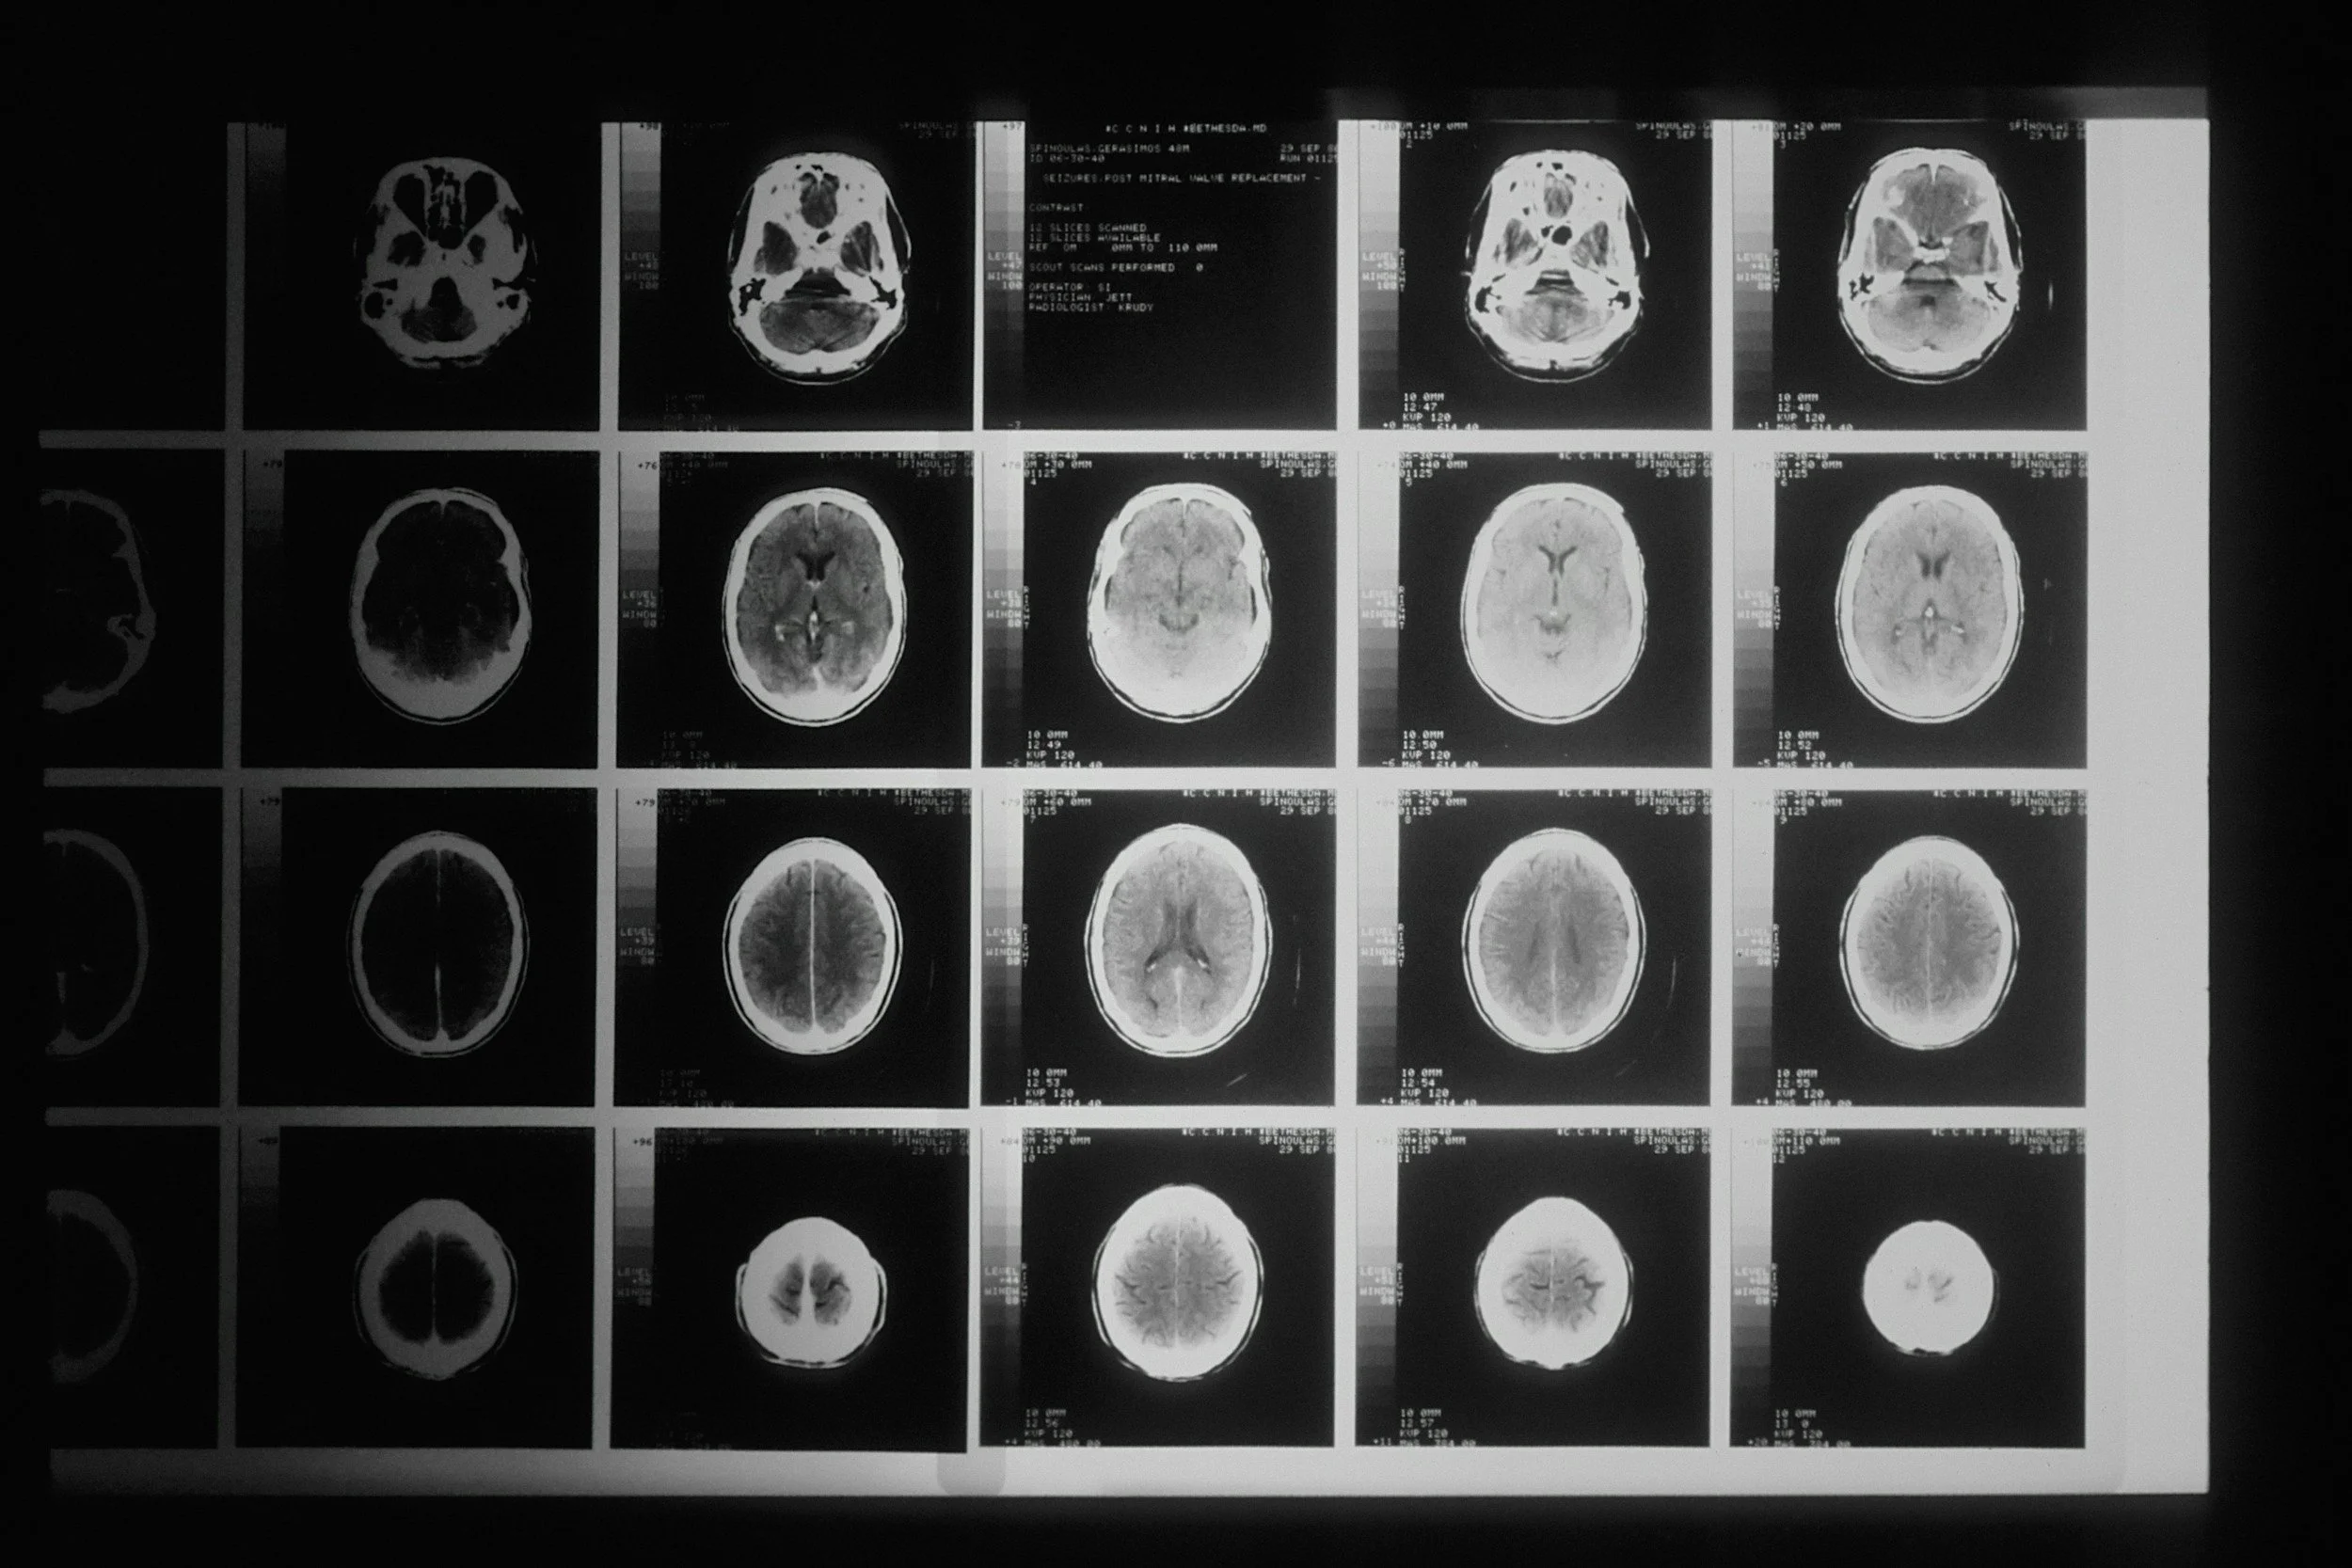

Brain & Nervous System

Explore the different lobes of the brain and how the brain sends signals to your body! Use the drop-down menu below to view our resources.